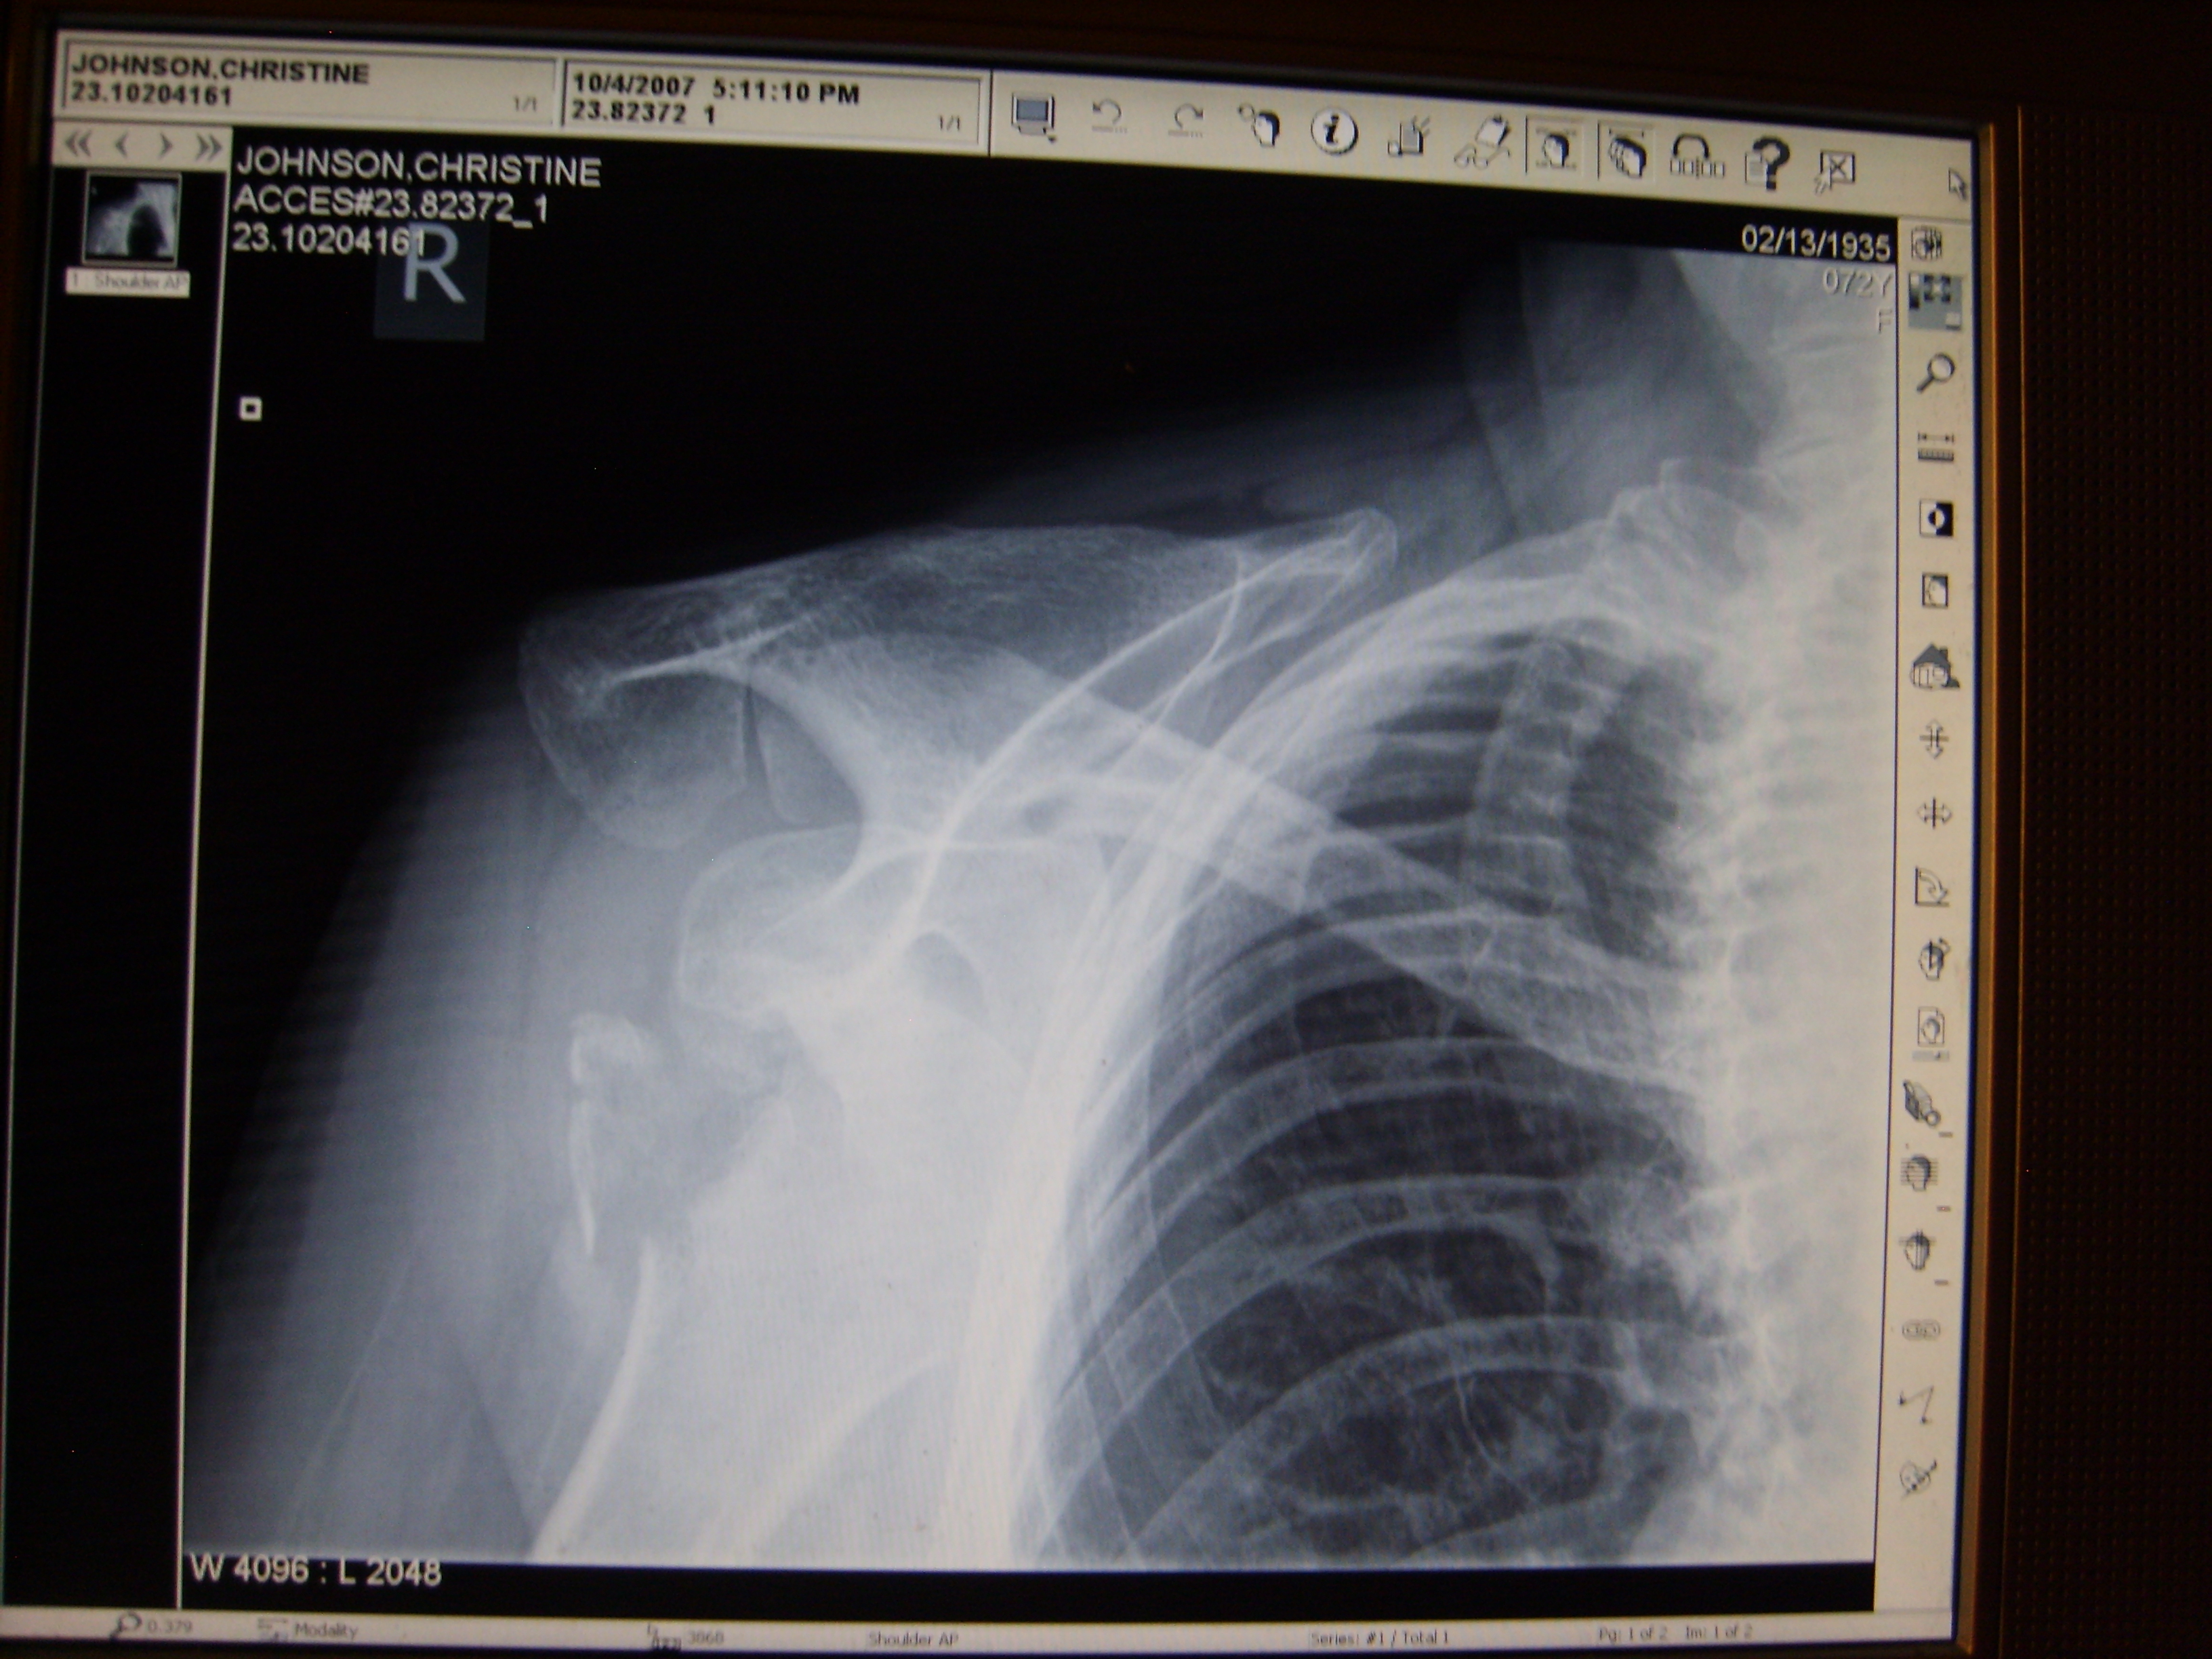

[The x-ray was taken on October 4, 2007, 11 minutes after leaving Dr. Stephen Chow’s office following mother’s ‘exam.’ It is clear, even to a layman, that the shoulder is dislocated and a large piece of bone is broken off and is floating in the area. While we were unable to view this initially as it required a special viewer for the CD we were given, a report was sent to Dr. Chow by the radiologist shortly after these x-rays were taken. Dr. Stephen Chow declared in his deposition that he did not see the report but did indicate that he suspected her arm was dislocated at the time he sent her home and rescheduled her appointment for the following week.]